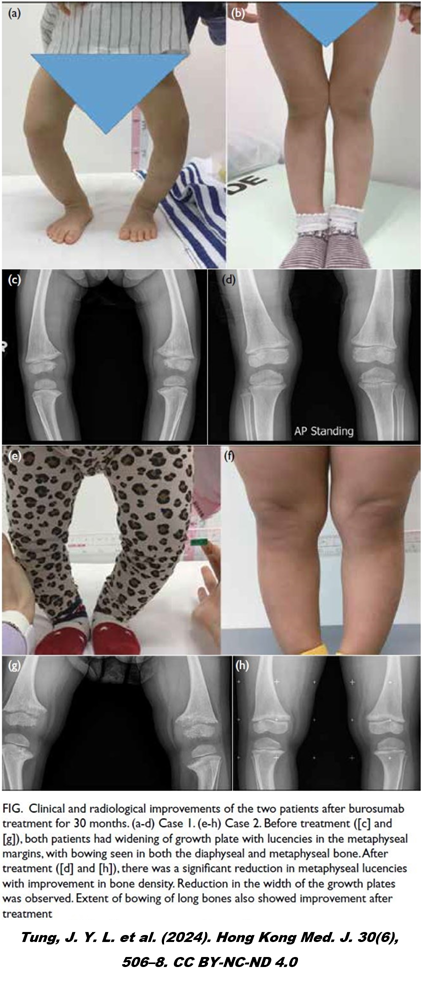

4. 유전성 저인산혈증 구루병 치료제, 크리스비타(Burosumab)는 보건복지부의 신속 등재 절차를 통해 도입된 1호 약제입니다. 이 약은 한 명을 치료하는데 필요한 비용이 연간 1~2억 원에 달할 만큼 고가지만, 기존 치료와 비교해 4배 이상 개선된 임상 결과가 보고될 정도로 효과가 뛰어납니다. (RGI-C 스코어 기준, 87% vs 19%)

5. 구루병은 칼슘과 결합해 단단한 결정 구조를 만드는 짝꿍, 인이 부족한 병입니다. 튼튼한 뼈를 만드는 데 칼슘이 가장 중요하긴 해도 시멘트가 부족하면 콘크리트가 부실해지듯 구루병 환자도 혈액 중 인이 부족한 탓에 뼈가 물렁물렁해집니다. 단단해지지 못한 뼈는 결국 체중을 견디지 못하고, 다리뼈가 휘어집니다. 특히 성장기 구루병 환아들은 적절히 치료받지 못하면 성장지연, 골절 위험, 거동 제한 등 치명적인 합병증이 발생할 가능성이 높았습니다.

GURU.png 구루병 환아의 휜 다리

13. 크리스비타는 이 호르몬 FGF23과 1:1로 결합하는 단클론 항체로 FGF23 수치를 낮추어 유전성 구루병을 치료합니다. 크리스비타를 맞은 환자는 신장에서 인의 재흡수가 일어나 인 수치가 증가하고 비타민 D의 활성화로 장내 인 흡수도 늘어남으로써 칼슘과 결합해 골이 튼튼해집니다. 환아들의 휜 다리도 무사히 교정됩니다.